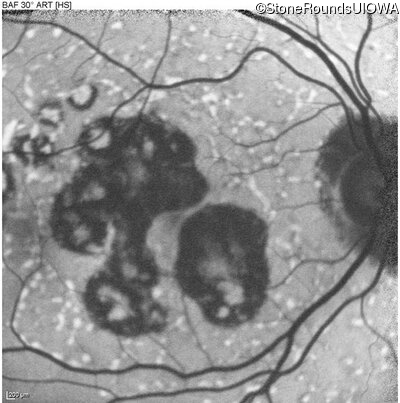

AR Stargardt Disease (IIA)

Age at visit: 59 years

This 59 year old man has noticed some blank spots near the center of his vision over the last 2 years.

Diagnosis & molecular findings

Disease Gene Allele 1 variant(s) Allele 2 variant(s) Inheritance mode

AR Stargardt Disease ABCA4 Leu2027Phe CTC>TTC IVS30+1321 A>G AR